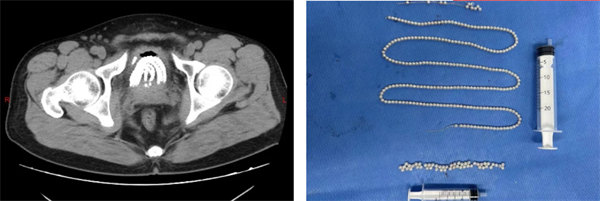

患者男44歲,因不慎將異物塞入尿道后無法自行取出,劇烈疼痛且排尿困難,隨緊急于寶雞市人民醫院泌尿病院就診。入院后,經過詳細的病史詢問和全面的術前檢查,泌尿病院專家團隊迅速制定了科學、合理的手術方案,決定采用經尿道膀胱異物取出術進行治療。

手術由泌尿病院泌尿外二科副主任杜喬主刀,在麻醉手術科的緊密配合下,通過先進的醫療設備和技術手段,成功將患者膀胱內的異物完整取出。術后,患者恢復良好,疼痛消失,排尿恢復正常。

圖片